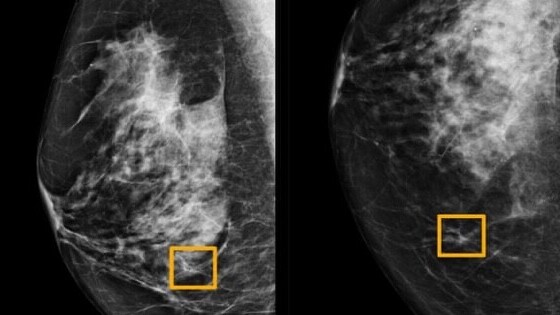

Google’s AI team has just developed a new system to scan X-rays to help radiologists in detecting breast cancer. The model was developed in partnership with DeepMind, Cancer Research UK Imperial Centre, Northwestern University, and Royal Surrey County Hospital.

The team used anonymized data from mammograms – low energy X-ray to detect breast cancer – of more than 76,000 women from the UK and more than 15,000 women from the US to train the AI model. Later, they tested it using a de-identified dataset of more than 25,000 women from the UK and 3,000 women from the US.

The AI helped reduce false negatives by 5.7 and 1.2 percent in the US and UK respectively. Plus, it also decreased the number of false positives by 9.4 and 2.7 percent in the US and UK respectively.

Google noted in its blog post the AI bested doctors in breast cancer detection despite having access to less amount of data. In the coming years, the company hopes to improve the accuracy of the model so it can aid hospitals in real-life detection.